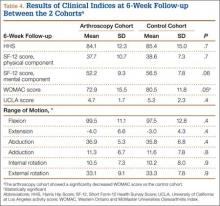

At 6-week follow-up, the arthroscopy cohort showed a significantly decreased WOMAC score compared with the control cohort (72.9 [SD, 15.5] vs 80.5 [SD, 11.8], respectively; P = .05). In addition, there was a trend towards a decreased SF-12 mental component score in the arthroscopy cohort (52.2 [SD, 9.3] vs 56.5 [SD, 7.8] in the control cohort; P = .06). However, none of the remaining clinical indices showed a significant difference between the 2 cohorts, and there was no difference in range of motion between the 2 cohorts at the 6-week follow-up visit (Table 4).